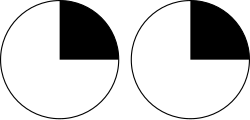

They carry visual information through two divisions (called upper and lower division) to the visual cortex (also called striate cortex) along the calcarine fissure. There is one set of upper and lower divisions on each side of the brain. If a lesion only exists in one unilateral division of the optic radiation, the consequence is called quadrantanopia, which implies that only the respective superior or inferior quadrant of the visual field is affected. If both divisions on one side of the brain are affected, the result is a contralateral homonymous hemianopsia.

| Fibers from the inferior retina (also called "Meyer's loop" or "Archambault's loop") | must pass through the temporal lobe by looping around the inferior horn of the lateral ventricle. | Carry information from the Superior part of the visual field | A lesion in the temporal lobe that results in damage to Meyer's loop causes a characteristic loss of vision in a superior quadrant (quadrantanopia or "pie in the sky" defect.) |

| Fibers from the superior retina* | travel straight back through the parietal lobe to the occipital lobe in the retrolenticular limb of the internal capsule to the visual cortex. | Carry information from the Inferior part of the visual field | Taking the shorter path, these fibers are less susceptible to damage. Damage caused is characteristically called "Pie in the floor" defect or inferior quadrantanopia. |